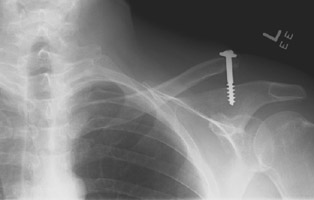

- Click on the image for a larger versionAAP radiograph of the left clavicle. There is grade III acromioclavicular joint separation. The screw was placed previously in an effort to prevent this injury.

Acromioclavicular separation refers to abnormal widening of the acromioclavicular joint. The injury is caused by direct trauma to the shoulder. The principal ligament to consider is the coracoclavicular ligament with a lesser role played by the acromioclavicular ligament. Ligamentous injury to the acromioclavicular joint is classified by Grade I, II, and III injuries. Grade I injury is termed sprain. Radiographs of both shoulders are acquired with stress views to see if there is abnormal widening of the acromioclavicular space (normal < 4 mm). Grade II injuries are termed subluxations and the acromioclavicular ligament is either severely torn or completely torn. The coracoacromial ligament remains intact meaning that only a small amount of superior migration of the clavicle is present when imaged with stress. Grade III injuries indicate that both the coracoclavicular and acromioclaviclar ligaments are torn with abnormal widening of the coracoclavicular space and superior migration of the distal clavicle relative to the acromion.